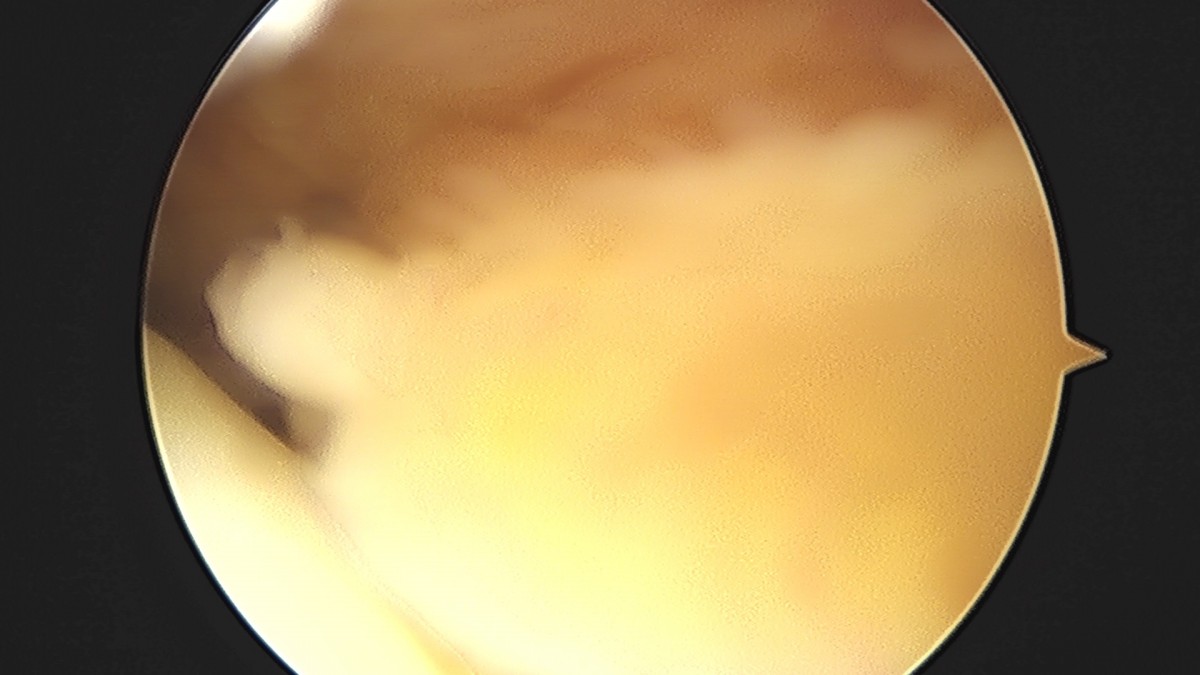

이재상원장님 무릎 전방십자인대 재건술 김태O 환자

작성자 최고관리자 댓글 0건 조회 679회 작성일 25-09-16 16:23